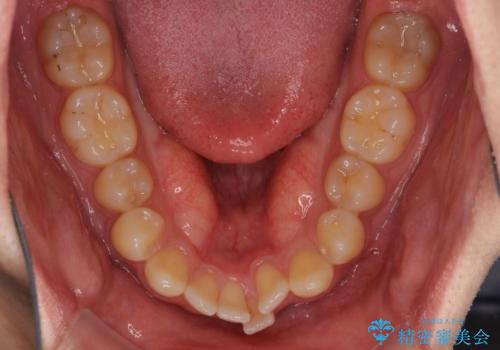

- 上下前歯のデコボコと深い咬み合わせを気にして来院された患者様です。

インビザラインによる上下歯列の拡大と、IPR(歯と歯の間を削る)にるスペースの獲得により、前歯のデコボコとディープバイトを改善することとしました。

もう少し下の前歯を整えたかったのですが、患者様の治療を早く終了させたいという希望により、細かい叢生を残しての終了となりました。